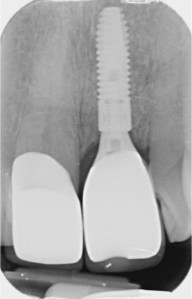

Single implant crowns

Single implant crowns are an excellent way to replace missing teeth. They do not damage the neighbouring teeth and last for a long period of time. These are usually screw retained to allow repair/replacement if there are any maintenance issues.